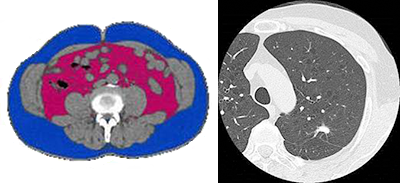

肺がんCT検査

2人の医師健康管理室医師と低線量肺がんCT読影医(放射線読影専門医)によるダブルチェックで読影しています。

10,780円 (肺がんCT + 内臓脂肪CT)

肺がんCT検査 (低線量CT)

当院、健康管理室ではオプションとして肺がんCTを準備しています。通常、肺がん検診は胸部レントゲン検査をメインに行ってきました。

レントゲン検査で描出される肺がんの大きさは、3センチが限界です。しかし、CT検査なら、5㎜程度の大きさから検出可能です。

肺がんは1993年以降、部位別死亡率第一位で、難治がんの一つです。初期の肺がんの検出はレントゲン検査のみでは限界があります。肺がんは種類と病期によって、予後が大きく変わります。

特に肺がんでは、3㎝未満 IA期(転移なし)であれば80%以上の5年生存率です。Ⅱ期であれば訳50%と大きく生存率が変わります。

当院健康管理室では、レントゲンでは発見しにくい3㎝未満( IA期 )の肺腺がんを発見し、早期治療につなげるために、低線量CTを推奨してす。